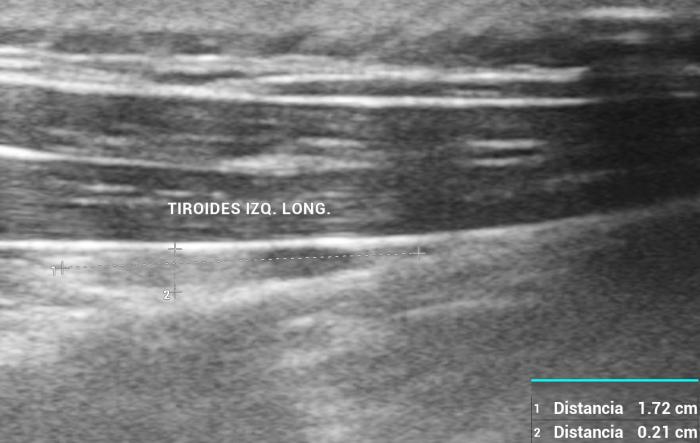

La glándula tiroides en perros y gatos está constituida por dos lóbulos situados a ambos lados de la tráquea cervical, con disposición longitudinal y una forma fusiforme o alargada que se extiende desde el cartílago cricoides hasta la entrada torácica superior2. En condiciones normales, cada lóbulo presenta contornos bien definidos, cápsula hiperecogénica delgada y parénquima homogéneo, con una ecogenicidad generalmente igual o ligeramente superior al músculo esternohioideo adyacente3,8. En la imagen transversal, los lóbulos suelen adoptar una configuración oval o ligeramente triangular (Figura 1); en longitudinal, se observa una forma alargada con extremos redondeados y orientación paralela a los vasos carotídeos y la tráquea1 (Figura 2).

En perros, el tamaño de la glándula tiroides muestra una correlación directa con el peso corporal. Algunos estudios han demostrado que las dimensiones tiroideas aumentan progresivamente en razas de mayor talla, manteniéndose proporciones constantes entre largo, ancho y alto de los lóbulos6. En gatos, la glándula tiroides suele ser más pequeña, delgada y elongada, con lóbulos habitualmente simétricos en animales sanos. La vascularización normal puede ser visualizada mediante Doppler color como un flujo periférico tenue y homogéneo, sin evidencia de hipervascularización focal ni penetración central4.

En cuanto a los parámetros ecográficos de referencia, estudios realizados en perros han determinado que los lóbulos tiroideos sanos presentan una longitud entre 13-23 mm, ancho de 3-8 mm y alto de 2-5 mm, con variaciones según raza y tamaño corporal6. En gatos, las dimensiones normales son más pequeñas y oscilan entre 10-17 mm de largo, y 2-4 mm de ancho y alto, dependiendo de la edad y el estado funcional10 (ver además la Tabla 1).

Ecografía tiroidea en perros: glándula normal, hipotiroidismo y neoplasias

En gatos clínicamente sanos, los lóbulos tiroideos se presentan simétricos, de forma alargada y tamaño reducido, con parénquima homogéneo e isoecogénico respecto al tejido muscular cervical adyacente1. Debido a su pequeño tamaño y a la posible interferencia de gas traqueal, se requiere una técnica meticulosa con transductores lineales de alta frecuencia para su correcta identificación12.